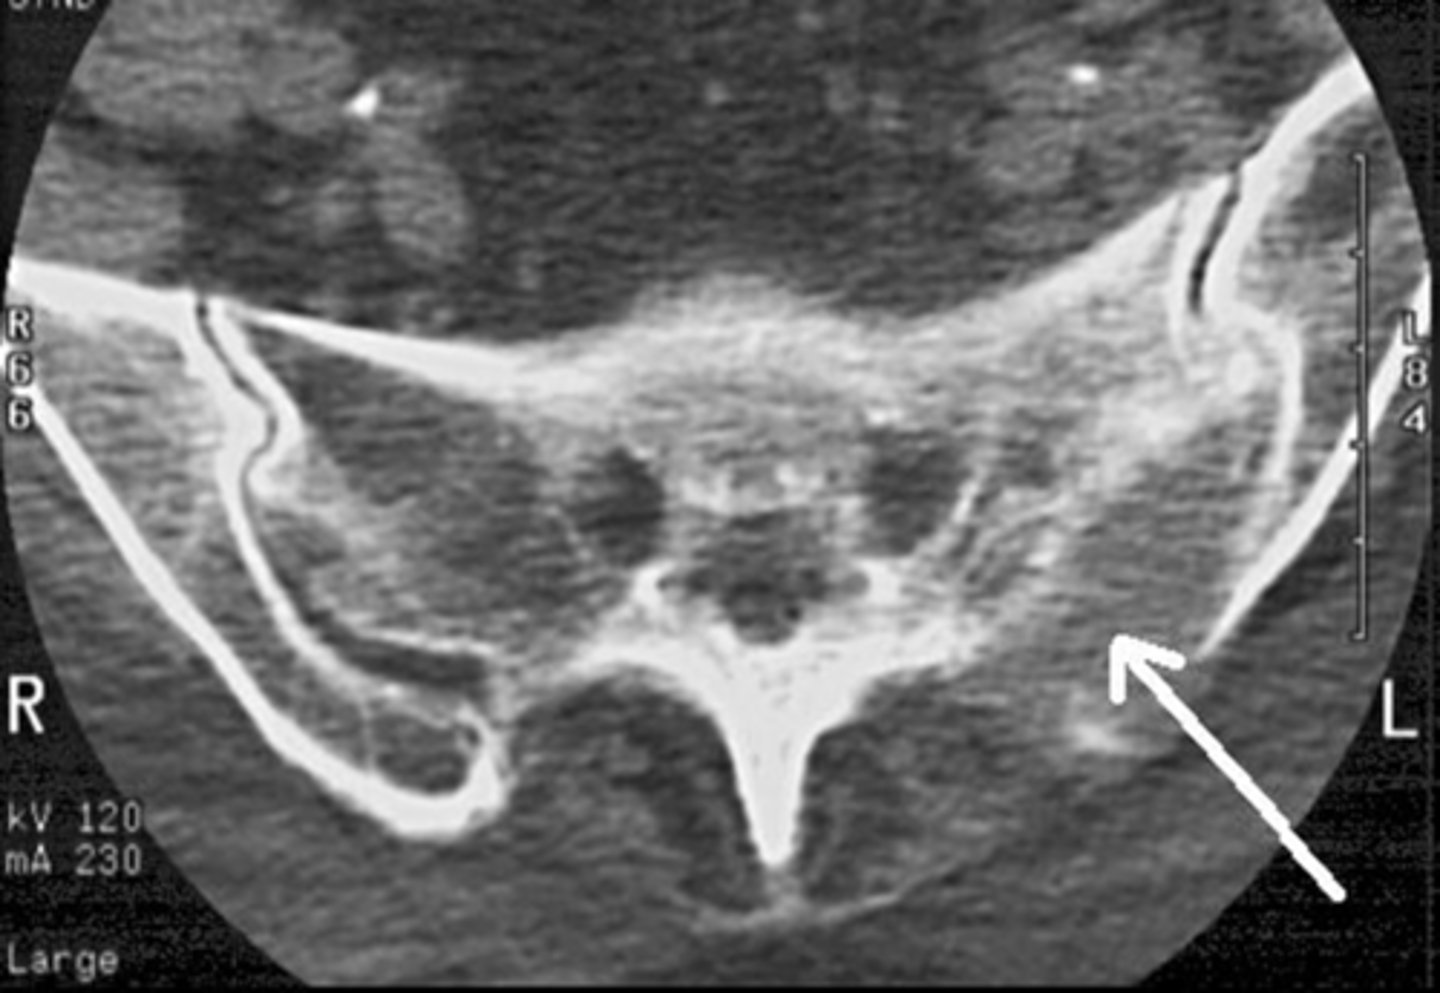

Lytic (Destructive)

What type of pathology is this

Osteolytic (destructive)

What kind of pathology is this

Destructive

What kind of pathology is this